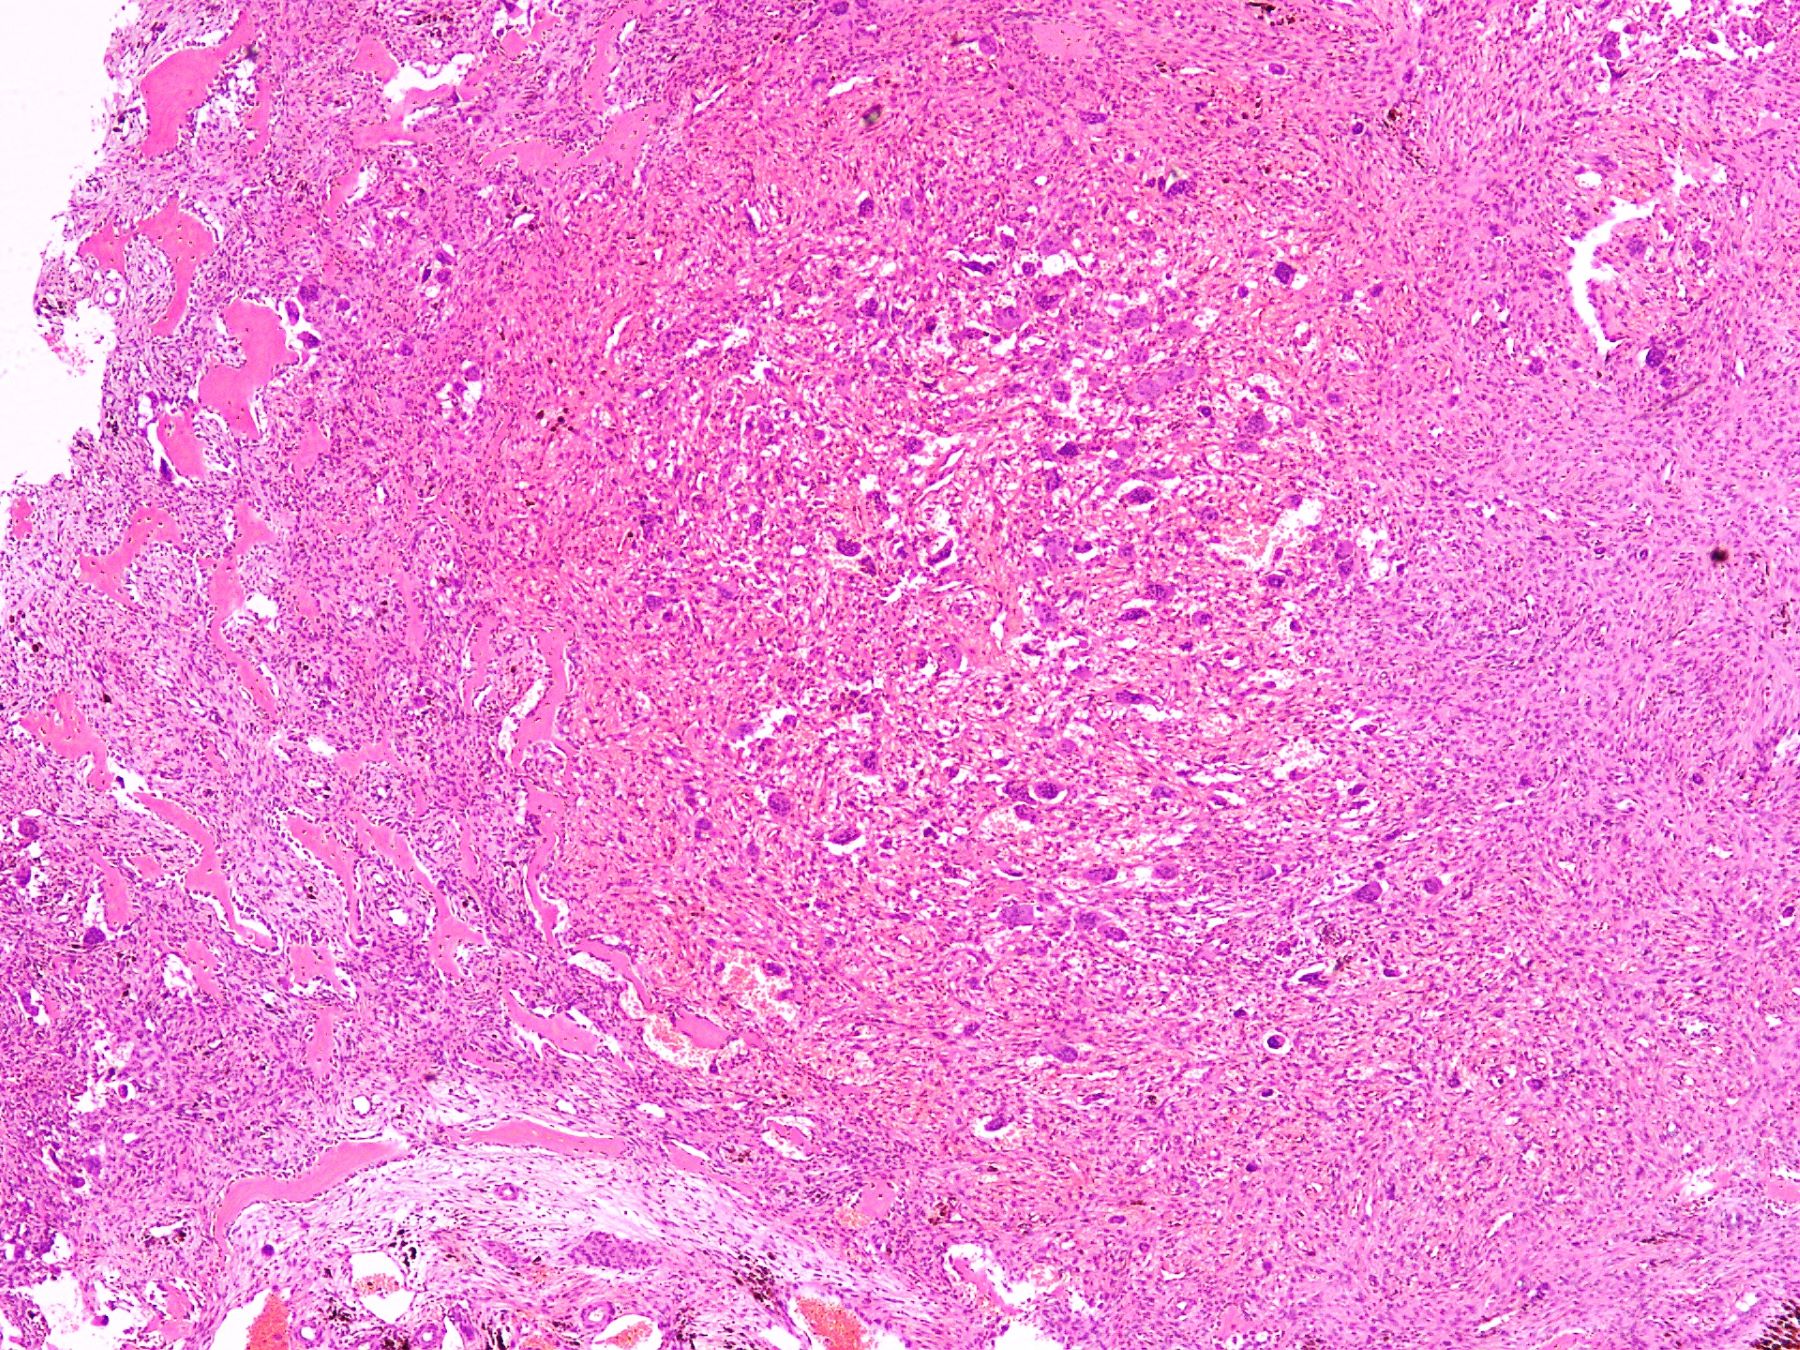

Microscopic (histologic) description

- Lobular pattern composed of groups and clusters of osteoclast-like multinucleated giant cells

- Vascular fibroblastic stroma

- Hemorrhage and hemosiderin deposits

- Tunneling resorption of adjacent uninvolved bone (J Int Oral Health 2015;7:50)

Microscopic (histologic) images

- Giant cell rich lesion (see comment)

- Comment: The lesion is composed of clusters of giant cells in a hemorrhagic fibroblastic stroma. Focal tunneling bone resorption is seen. This feature, along with multiple lytic lesions on radiology, strongly favor brown tumor of hyperparathyroidism. Correlation with clinical history, radiological findings and serum PTH and calcium levels is recommended.

A 50 year old woman presented with a swelling on the right side of her face that gradually increased in size over last 3 years. It was associated with pain, trismus and inability to open her right eye. She also had history of frequent headaches, abdominal pain and renal stones. Xray revealed a lytic lesion within the right mandible. Incisional biopsy was performed and microscopic examination revealed a lesion (shown above). The most likely diagnosis is

B. Brown tumor of hyperparathyroidism. The photomicrograph shows a lesion composed of bony trabeculae showing resorption along with scattered osteoclast-like giant cells in a vascularized spindled stroma. These microscopic findings with above mentioned clinical and radiological features are characteristic of brown tumor of hyperparathyroidism. Aneurysmal bone cyst affects young adults and shows large blood filled spaces with intervening septae containing fibroblasts and giant cells. Central giant cell granuloma produces radiolucent lesions in children and young women and shows osteoclast-like giant cells near hemorrhagic areas, cellular vascular and fibrous stroma and new bone formation at edge of lesion. Cherubism shows bilateral involvement of mandible and maxilla in young individuals and histology is similar to central giant cell granuloma. Giant cell tumor rarely affects mandible and shows uniform distribution of osteoclast type giant cells among mononuclear cells.